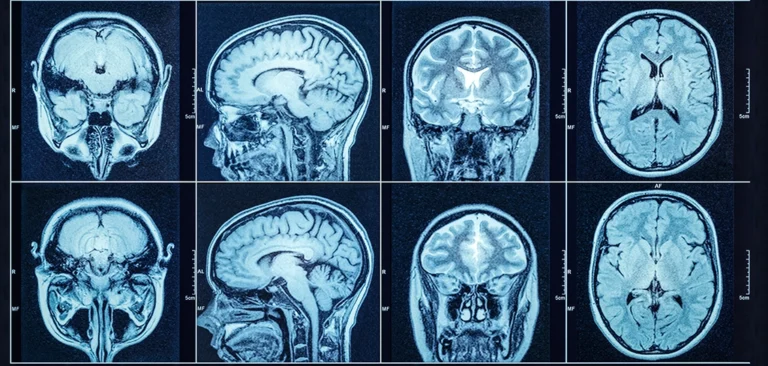

When a head injury occurs, it can be hard to know what’s happening inside the skull. A head CT scan offers a clear, detailed look at the brain, helping healthcare providers understand any potential damage. This type of scan can identify signs of trauma, like bleeding, swelling, or fractures, and provide important clues about the severity of an injury.

A head CT scan can highlight different types of injuries within the brain and skull. It helps detect bruising, blood clots, fractures, or any shifts in brain tissue caused by a traumatic impact.

A CT scan uses detailed cross-sectional images to detect bleeding inside or around the brain. It can show whether blood is pooling in certain areas, which may increase pressure inside the skull.

Swelling is another key concern after a head injury, and a CT scan can reveal if the brain is pressing against the skull or shifting from its normal position. If a fracture is present, a head CT scan can provide a clear view of any breaks or cracks in the skull that might pose additional risks.

Radiologists carefully study each image to look for abnormalities that could indicate an injury. This includes analyzing the brain’s structure, checking for any shifts, swelling, or unusual dark or bright areas that may signal bleeding or bruising.

They also look at the spaces between brain tissue and the skull, ensuring there’s no excessive pressure or trapped fluid. Even small changes in brain appearance can provide important clues about the presence and extent of potential brain trauma.

CT images use varying shades of gray to distinguish between different types of tissue, fluid, and bone. Blood from an internal bleed may appear brighter than surrounding areas, while swelling might appear as a darker region pressing against the skull.

Fractures in the skull are also visible, helping to determine if an external impact caused additional complications. These visual details allow specialists to pinpoint exactly where an injury has occurred and whether immediate care is needed.